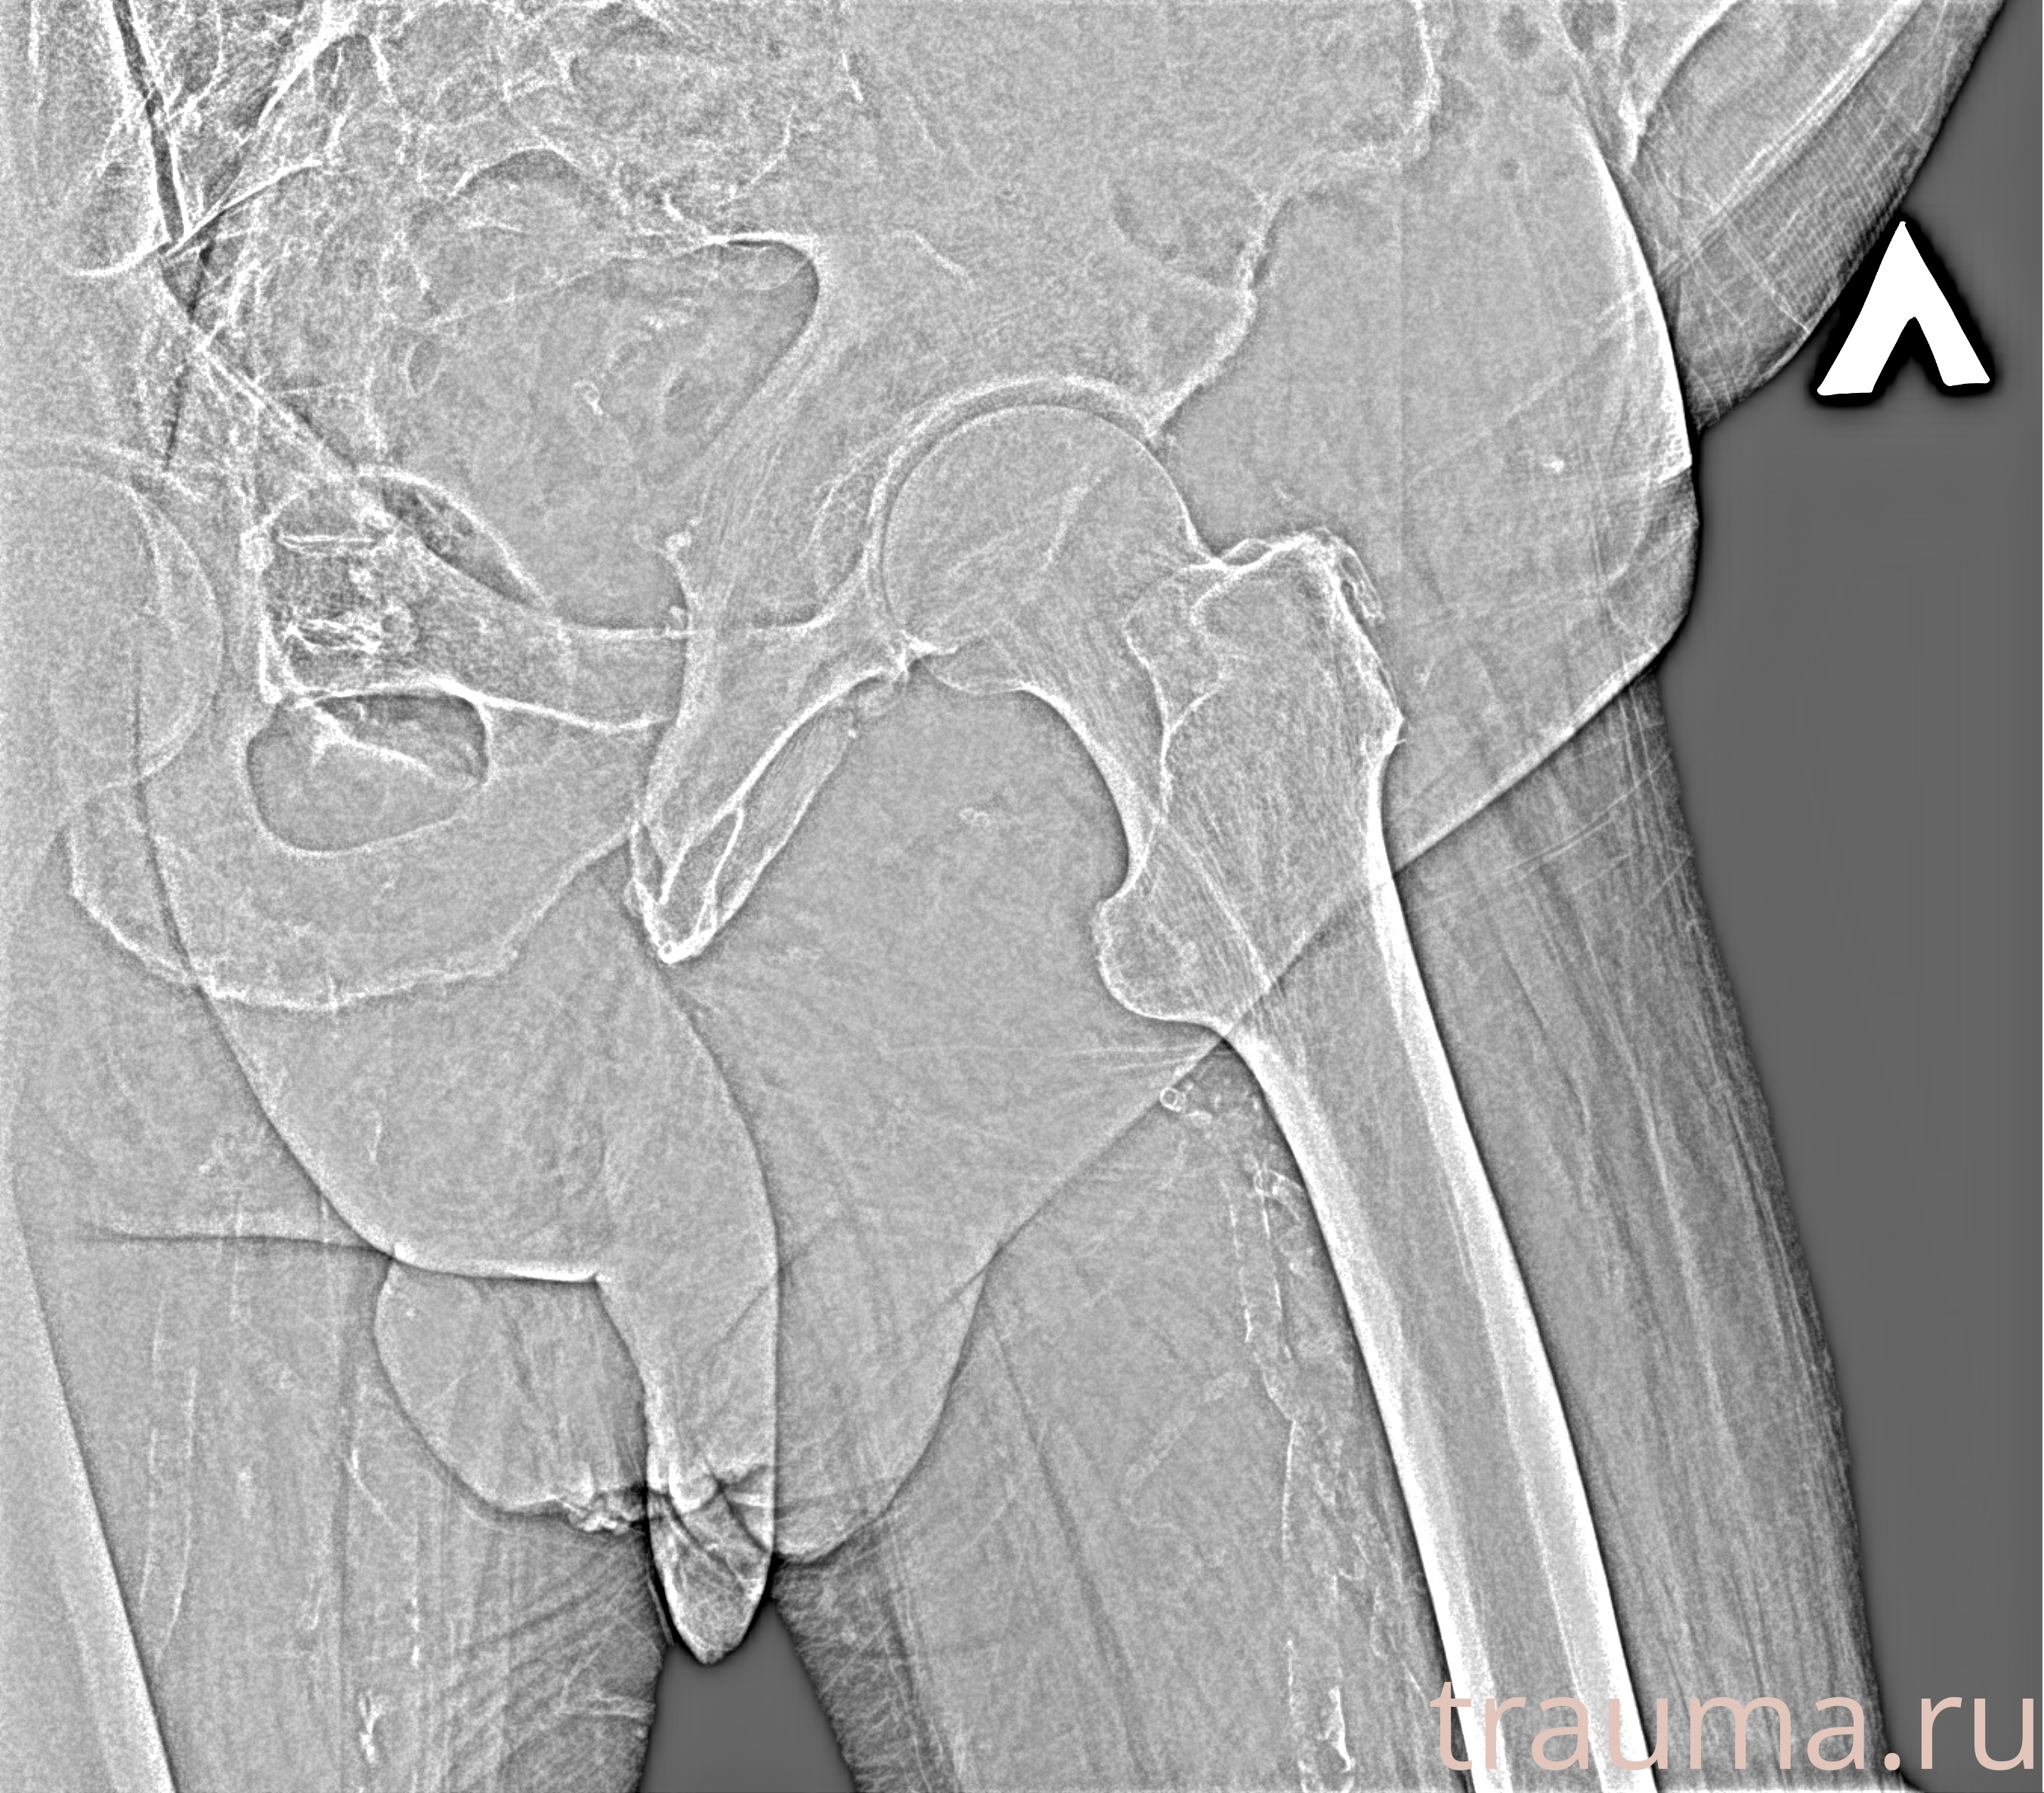

Рентген на дому: по вашему адресу приезжает врач-рентгенолог, травматолог-ортопед с мобильным рентгеновским аппаратом, проводит диагностику травмы или заболевания, делает необходимые рентгенограммы, дает рекомендации по дальнейшему лечению. Получить качественные снимки в домашних условиях возможно благодаря уникальной методике, разработанной МосРентген Центром для института  Склифосовского